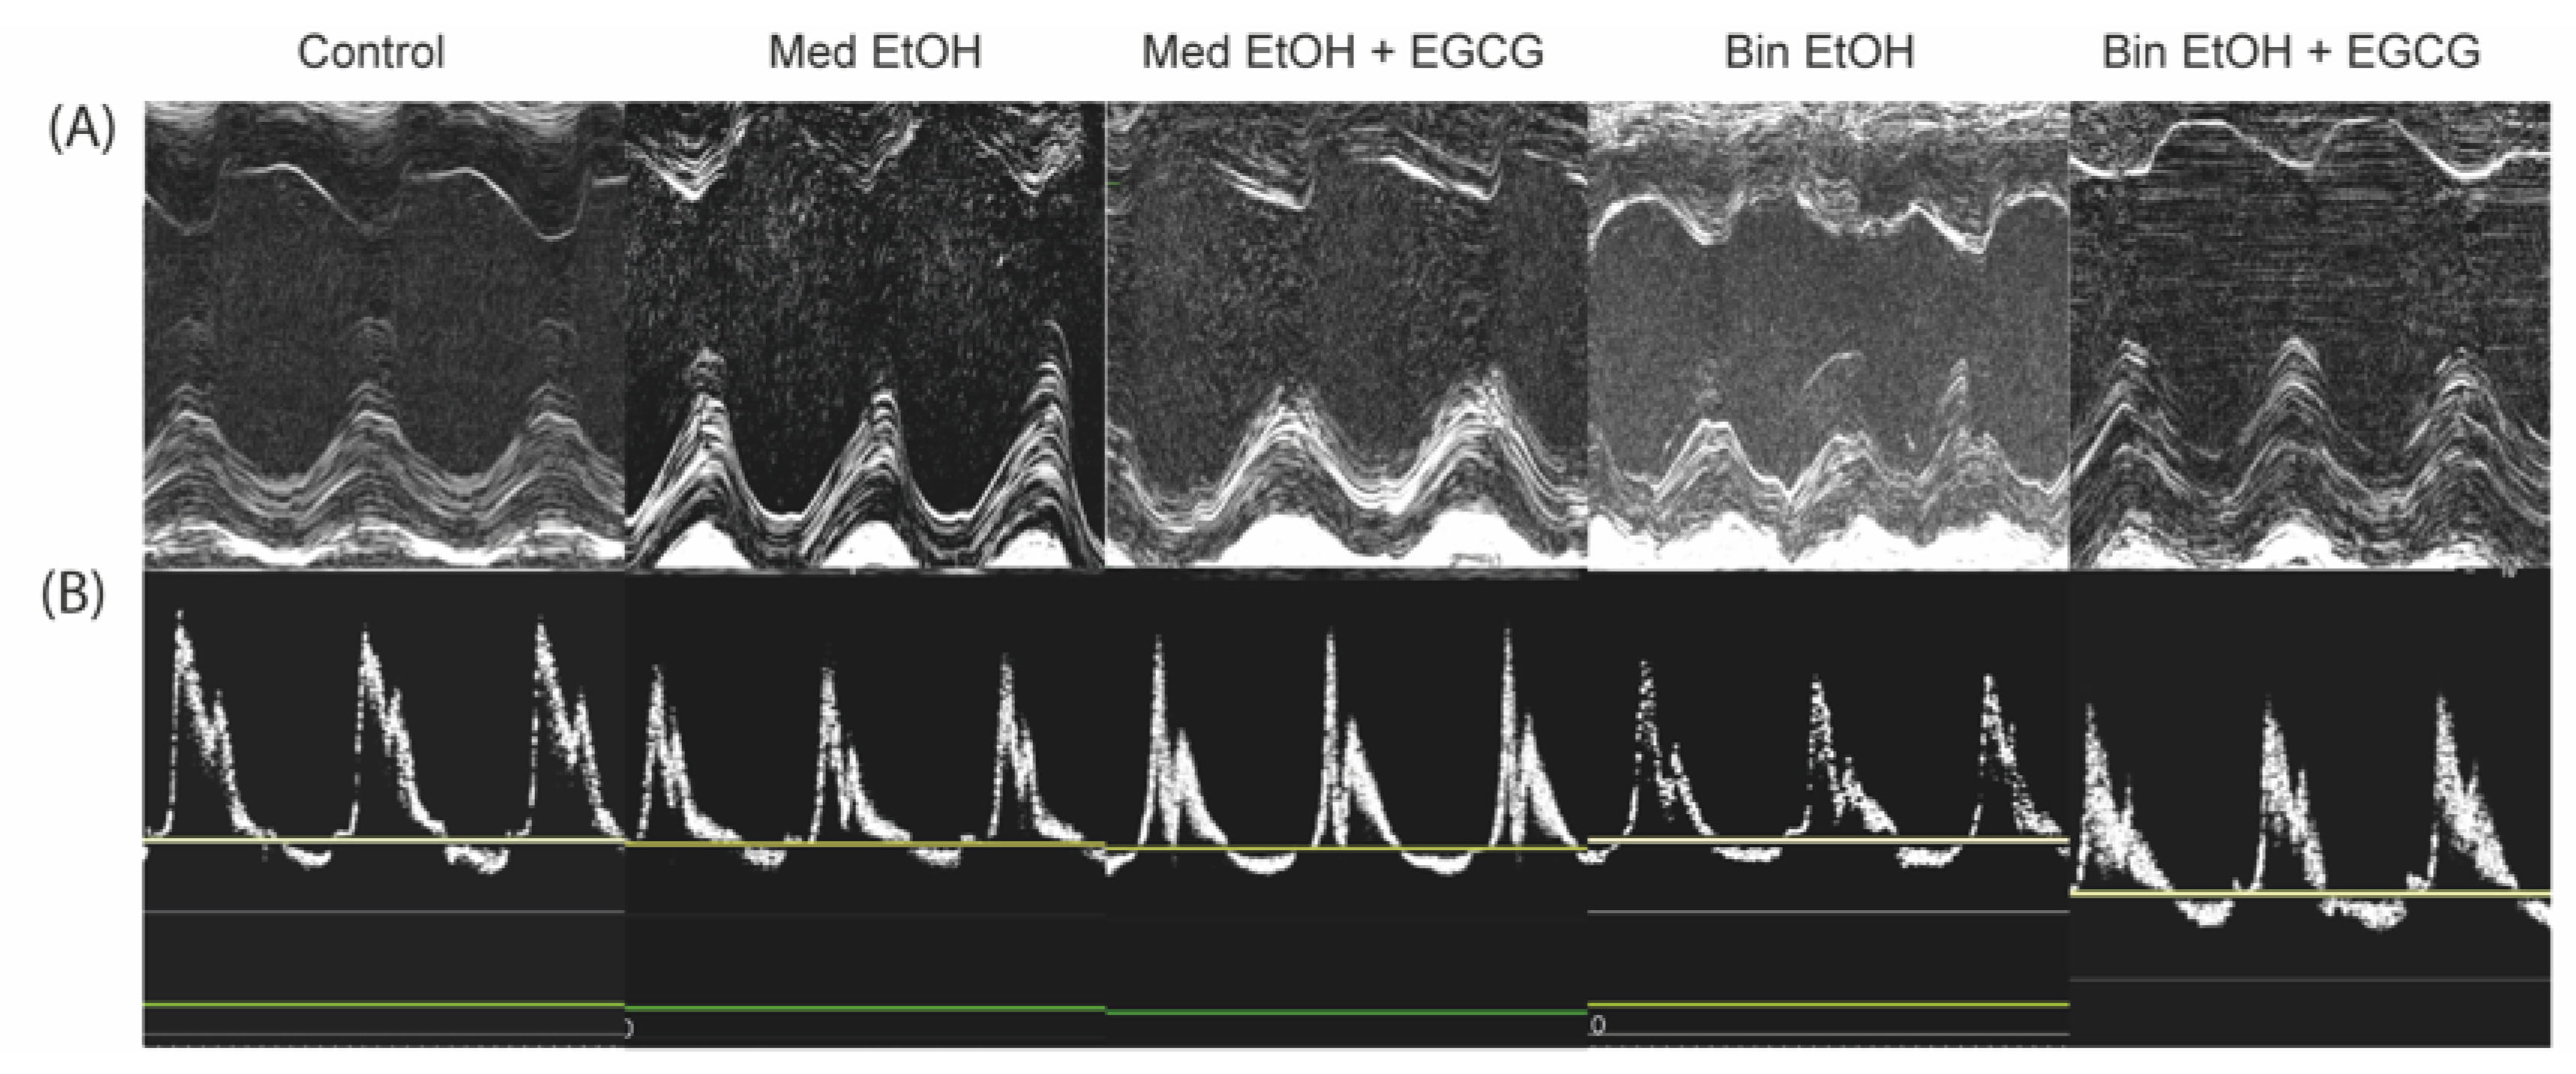

Representative results of systolic (Figure 7A) and diastolic (Figure 7B) heart function evaluated by echocardiography for each offspring experimental group. The results in Table 1 include 89 echocardiographies: 33 from the control group, 16 from the Med EtOH group, 16 Med from the EtOH + EGCG group, 17 from the Bin EtOH group, and seven from the Bin EtOH + EGCG group.

Figure 7.

Echocardiographic images from mice with different patterns of prenatal alcohol exposure -Mediterranean (Med EtOH) or binge (Bin EtOH) -, compared with controls and prenatal alcohol exposure plus postnatal epigallocatechin-3-gallate treatment (Med EtOH + EGCG) and (Bin EtOH + EGCG). (A): Representative M-mode images on parasternal short-axis view to assess systolic function of the heart of experimental mice; (B): Representative images of pulse-wave Doppler of mitral inflow to assess diastolic cardiac function in experimental mice. Med: Mediterranean drinking pattern; EtOH: ethanol, Bin: binge drinking pattern; EGCG: epigallocatechin-3-gallate.